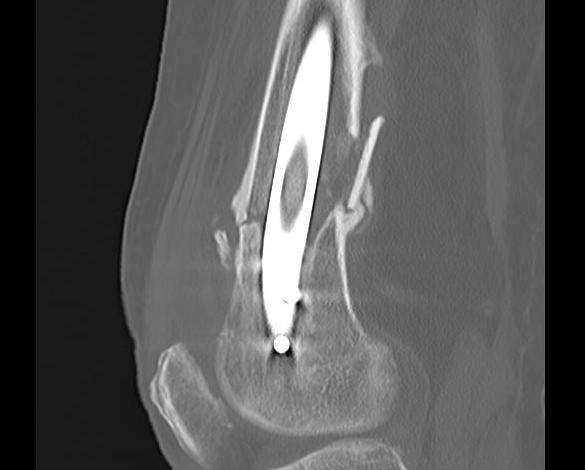

Type C: Complete articular

Xray / CT

Dual plate

Indications

Significant comminution

Loss of medial cortical buttress

Results

- 21 comminuted distal femur fractures

- increased union rates with double v single plate

- increased revision rate with single plate

Complications

Nonunion

Incidence

Kiyono et al. J Orthop Surg Res 2019

- increased nonunion with medial fracture gap > 5 mm

- 96 patients

- more rigid plate screw constructs associated with nonunion